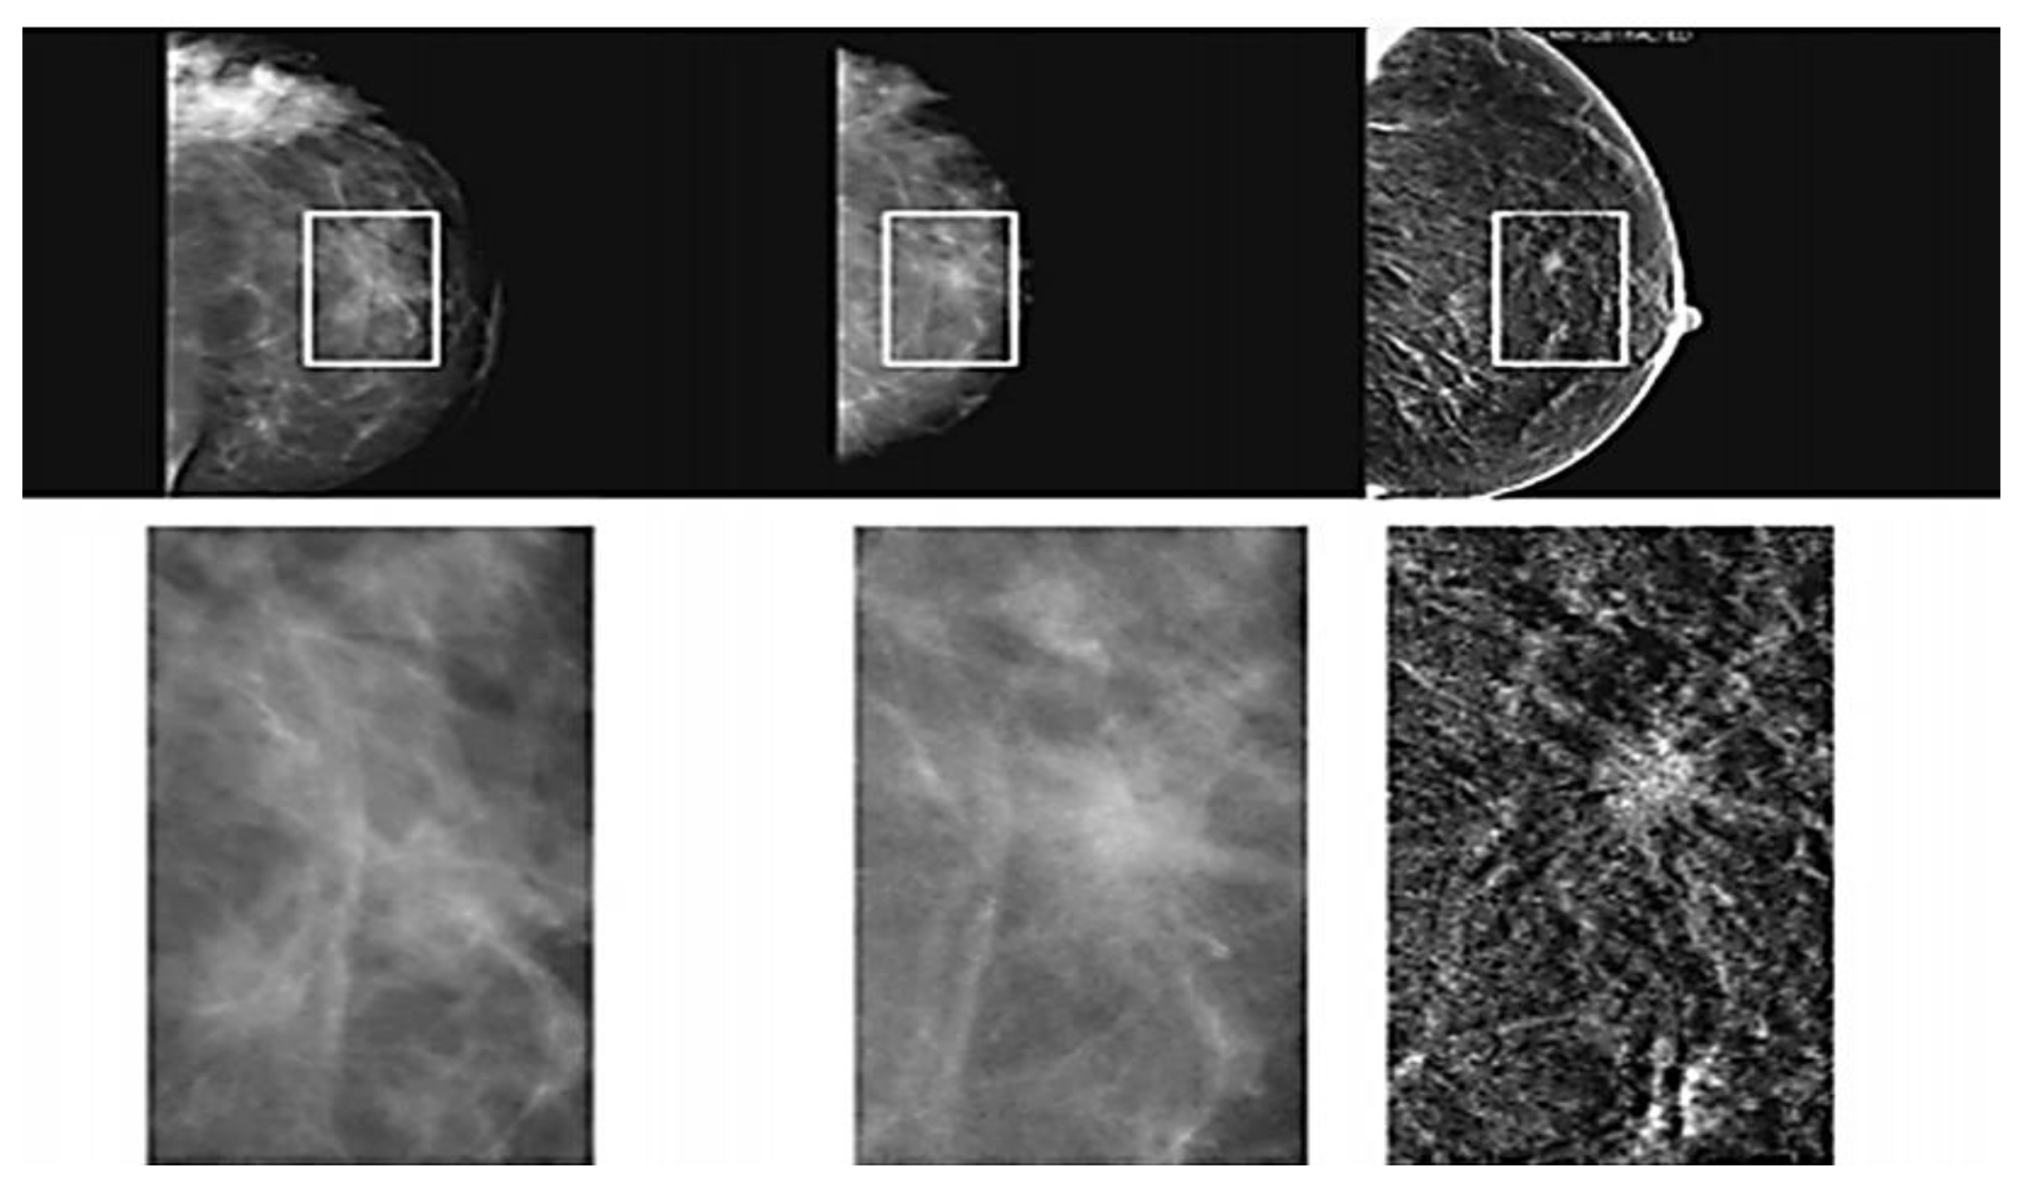

2.1.3. Magnetic Resonance Imaging (MRI)

Magnetic Resonance Imaging (MRI) is a medical imaging technique that records changing strong magnetic fields and radio waves to produce detailed images of the organ and soft tissues of the human body [38,47,48]. MRI is the most effective imaging modality that offers precise accuracy and sensitivity in detecting structural abnormalities of the body compared to the other technique, as shown in Figure 6 [49,50,51]. However, MRI is an expensive technology, and a waiting list is often long. MRI is a painless radiology procedure and does not use harmful ionizing radiation of X-ray. The MRI scanner machine is a large horizontal tube surrounded by a circular superconducting magnet where one patient enters (lie down in bed) [52] and running through the magnet from front to back that assist by the technician or a radiographer. During this procedure that take around 30–45 min, some patients can experience discomfort or fear of enclosed spaces (claustrophobia). MRI creates a powerful magnetic field that forces the protons in the body to align with that field. Then, a radio-frequency current is pulsed through the patient’s body that disrupts the proton and forces it into 90-degree or 180-degree realignment with the static magnetic field. The scanner can identify the energy signal from the patient’s body when the radio frequency is switched off. On the computer screen, these impulses were used to create visual images [53] as shown in Figure 7. Combining mammography, MRI, and certain clinical techniques yielded the best sensitivity 94.4%. The highest level of accuracy attained was 75.6%, implying that one out of every four diagnoses is incorrect [46]. The comparison of diagnostic performance of different breast tumor detection techniques is present in Table 4.

Figure 7.

Typical finding of MRI-detected breast cancer (arrow) [50].